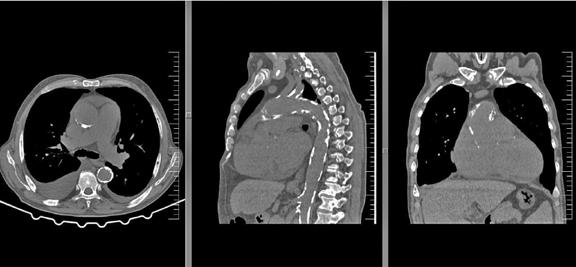

De exemplu, disfuncția ventriculară indusă de efort apare frecvent secundar ischemiei miocardice, unde se identifică o creștere a presiunii de umplere ventriculară și o scădere a debitului cardiac, cu apariția ulterioară a simptomelor de insuficiență cardiacă (dispnee). În acest sens, se recomandă evaluarea amănunțită a leziunii ischemice coronariene prin efectuarea angiografiei coronariene prin tomografie computerizată (angio CT coronarian) sau a coronarografiei/ angiografiei coronariene ce reprezintă standardul de aur pentru confirmarea diagnosticului de boală coronariană dar și pentru stabilirea deciziei de revascularizare, conduita terapeutică optimă la această categorie de pacienți.